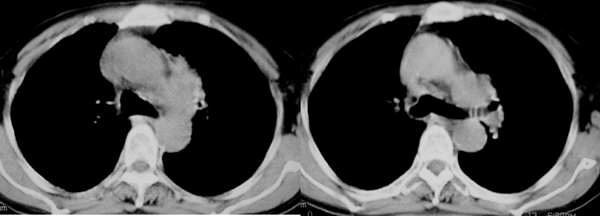

不是我想做强化,我对体部病灶一直是强调要强化的,可皮试第5分钟患者有头痛,加上高龄,为了减少医疗纠纷就只好不做。望战友理解。此病灶我觉得首先要明确是来1,自于肺内还是纵隔内?2,在扫描层内见右肝与隔之间内见囊壮均匀水样低密度区,于肝关系密切,首先考虑是肝囊肿{由于没有强化故不好说,只有建议患者行进一步检查!}

肝内巨大低密度占位,因无增强,就平扫考虑:1.肝血管瘤;2.肝囊肿;肝转移瘤;

郁闷!病灶和主动脉弓是宽基底相连,但主动脉弓壁是清晰可见;肺窗示病灶边缘见不规则毛刺样改变;肝左叶见巨大囊性病灶。我考虑胸部病灶是纵隔型肺癌,肝内病灶不好说是啥。

影象表现:左上肺纵隔旁可见一形态略不规整的软组织肿块(上自主动脉旁,下至左肺动脉上层面);

密度较均匀;最大层面与主动脉弓呈宽基底,但与其可见一线状低密度影分割,下方与尖后段

支气管内侧壁和左上肺静脉分界不清(尖后段支气管未见明显狭窄)双肺血管纹理明显增多

影象诊断:考虑纵隔型肺癌伴纵隔淋巴结转移.肺内炎变待除外.肺内转移建议hrct

病灶和主动脉弓是宽基底相连,但与主动脉弓壁之间的脂肪间隙清晰可见;肺窗示病灶边缘有不规则毛刺样;左肺叶段肺气肿;左侧横膈升高。右肺中叶炎变;结合病史考虑纵隔型肺癌可能性大。其他的难说!

左上肺纵隔旁可见一形态略不规整的软组织肿块,与主动脉弓壁之间的脂肪间隙清晰,肺窗示病灶边缘有不规则毛刺样改变,右肺中叶炎症。综合病史考虑纵隔型肺癌。

部分见肝内大圆形低密度灶影,包膜完整,考虑肝囊肿。

因为患者不宜强化,故行b超,报告为肝囊肿。18楼战友说得也有道理,但我想按淋巴引流的途径看{因为肺内炎性病灶主要在右恻}有点不符号,反过来推:如果把它作为淋巴结应该是多个增大淋巴结的融合,但其密度较均匀,未见坏死。{仅供讨论!}谢谢各位战友的!参与!!!